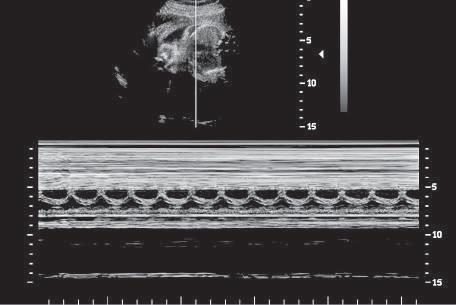

Another simple form of imaging, M-mode (motion-mode) ultrasound, displays echo amplitude and shows the position of

changes of echo amplitude and position with time. Display of changes in echo position is useful in the evaluation of rapidly moving structures such as cardiac valves and chamber walls. Here, the three major moving structures in the upper gray-scale image of the fetus are recorded in the corresponding M-mode image and include the near ventricular wall (A), the interventricular septum (B), and the far ventricular wall (C). The baseline is a time scale that permits the calculation of heart rate from the M-mode data.

moving reflectors (Fig. 1.12). M-mode imaging uses the brightness of the display to indicate the intensity of the reflected signal. The time base of the display can be adjusted to allow for varying degrees of temporal resolution, as dictated by clinical application. M-mode ultrasound is interpreted by assessing motion patterns of specific reflectors and determining anatomic relationships from characteristic patterns of motion. Currently, the major application of M-mode display is evaluation of embryonic and fetal heart rates, as well as in echocardiography, the rapid motion of cardiac valves and of cardiac chamber and vessel walls. M-mode imaging may play a future role in measurement of subtle changes in vessel wall elasticity accompanying atherogenesis.